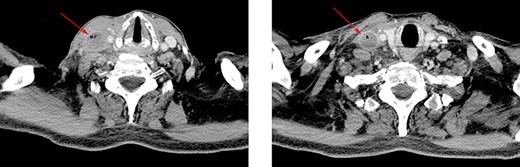

Coronal and sagittal images showing the jugular thrombosis along the neck.

Forty-eight hours later, the patient presented self-limited abdominal bleeding probably related to high dose of low molecular weight heparin (LMWH), which was treated conservatively. At the same time, hiccups appeared. It initially responded positively to haloperidol and chlorpromazine, but it progressed in frequency and intensity, becoming uncontrollable. A CT scan confirmed the absence of intraabdominal complication, and the patient was admitted to the intensive unit care to intensify hiccup treatment. During the next days, he started with fever peaks. Bacteraemia related to CVC was diagnosed, as well as inflammatory signs on the right jugular venous access. Due to the previous findings, a cervicothoracic CT was performed showing a thrombus and air bubbles into the right jugular vein. This conditioned a dilatation of an area of the vein intimately related to the phrenic nerve.

Different agents have been associated to hiccups etiology, which stimulate central or peripheral structures of the hiccups’ reflex arc [1, 2, 4]. Some of these agents, such as trauma, tumors, infections or metabolic diseases, produce persistent hiccups (lasting more of 48 hours) or even untreatable (2 or more months lasting) [1, 4]. In this patient, hiccup etiology was difficult to identify and resulted in a diagnostic challenge, because fever and cervical inflammatory signs appeared days after hiccups. When signs and symptoms came together, a cervical TC was performed, concluding that manipulation of CVC led to a septic thrombosis of internal jugular vein, its dilatation and, finally, the direct compressive stimulation of phrenic and vagus nerves (Figs. 1 and 2). Topaz et al described a case of uncontrollable hiccups after the insertion of a catheter into jugular internal vein because of the compression of phrenic nerve due to a hematoma [2, 3].